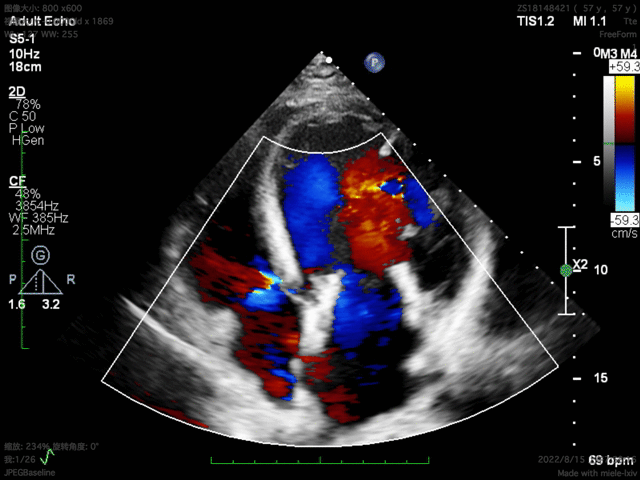

患者基线资料

该例患者为57岁男性,因扩张型心肌病合并严重心功能不全,并伴有高尿酸血症、高脂血症等疾病。超声心动图评估提示二尖瓣重度反流、轻微主动脉瓣反流与轻微三尖瓣反流,LVEDD 83mm,LVESD 73mm,LVEF 34%。二尖瓣反流机制为功能性反流,有效反流口面积为0.49cm²,反流量93mL,瓣口面积为6.7cm²。

术前超声评估

该手术采用左侧第五肋间微创切口心尖入路,透视下经导丝置入输送系统,逐步释放瓣膜。透视及TEE确认瓣膜位置满意后撤出输送系统,二尖瓣瓣膜形态及工作状态良好,复查左心室造影,提示无瓣周漏,无左室流出道梗阻,左右冠状动脉显示良好,未受任何影响。

患者术后30天随访状态良好,随访显示左心室逆重构,左心室功能伴左心室结构显著改善,全面达成包含二尖瓣反流程度降低、心功能改善等有效性指标。人工二尖瓣工作正常,支架结构及形态稳定,锚固良好无位移,无瓣周漏。瓣叶开闭形态良好,血流动力学表现优异,平均跨瓣压差仅1mmHg。